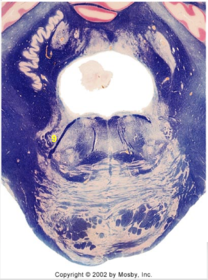

| Head of caudate | |

| Anterior commissure | |

| Thalamus | |

| Substantia nigra | |

| Optic tract | |

| Dentate nucleus | |

| Pons | |

| Longitudinal pontine fibers | |

| Uncus | |

| Superior cerebellar peduncle | |

| Red nucleus | |

| Corticospinal tract (dark) | |

| Pontine nuclei (pale) | |

| Transverse pontine fibers (dark) | |

| Inferior olive | |

| CTT | |

| Medial lemniscus | |

| Nucleus cuneatus | |